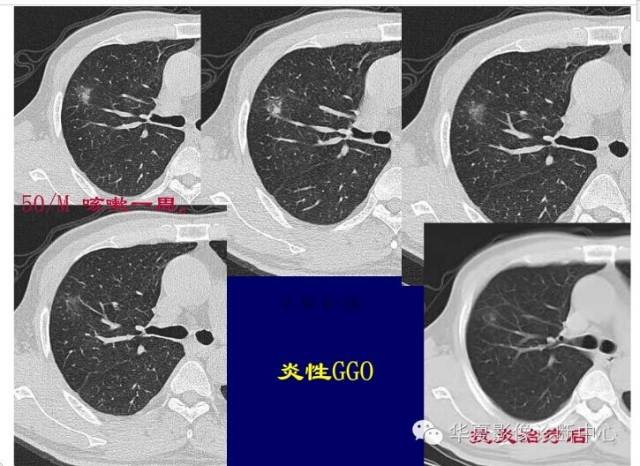

GGO的边缘模糊,考虑炎性病变

对于不好定的,不典型的一律建议抗炎后复查

如果不看边缘是否清楚,就好像癌肿

但是一看边缘就是炎性病变

大家记住了,边缘模糊的GGO首先考虑炎症